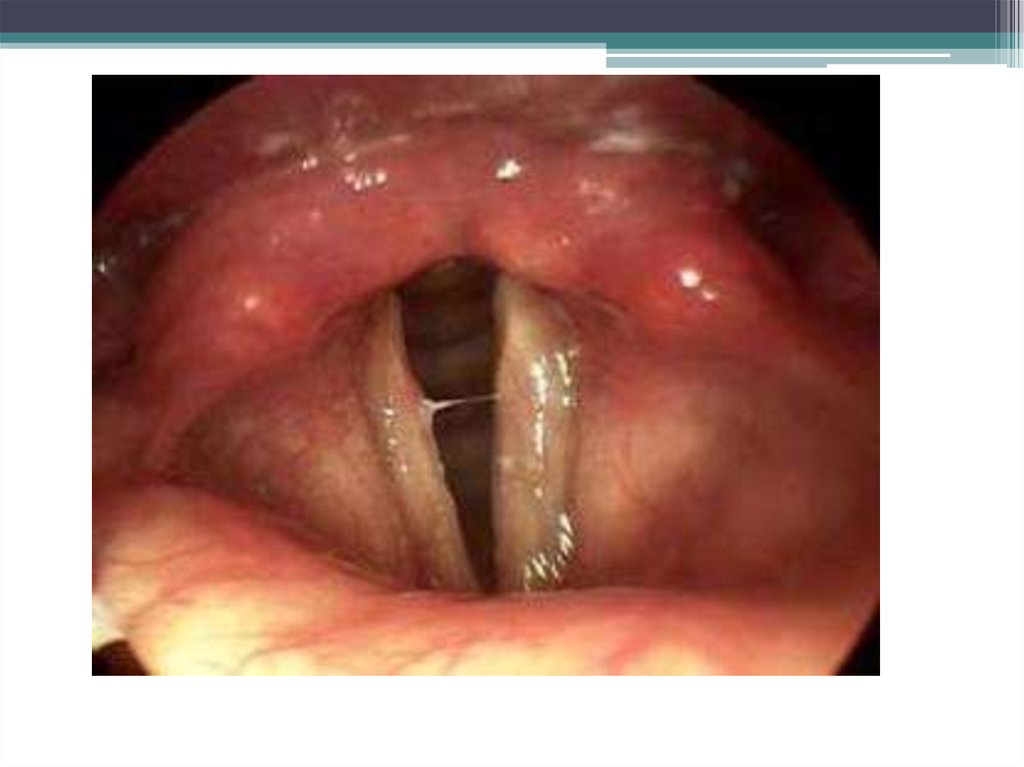

7. Патоморфологические изменения

В

области

надгортанно-черпаловидных

хрящей,

голосовых

связок,

между

надгортанным хрящом и языком имеются

студенистые

припухлости,

бледные

или

окрашенные в ярко – красный цвет. Они

вдаются в просвет голосовой щели и суживают

ее. При разрезе их слизистая оболочка обычно

собирается в складки. Часто наблюдается

отечность слизистой оболочки глоткт, трахеи и

корня языка.

8. Диагноз

• На основании анамнеза и характерных

клинических признаков.

• Осмотр гортани у крупных животных с

помощью

электроларингоскопа

непосредственно через рот

• У мелких животных – непосредственно через

рот с помощью гортанного зеркала.

• У КРС – путем пальпации области гортани